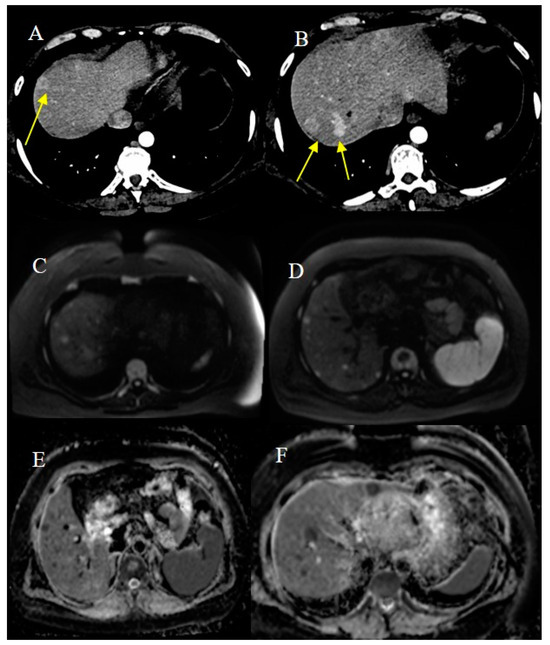

2.7. Metastatic Presentation of Small Bowel Tumors

- Attiyeh, M.A.; Malhotra, G.K.; Li, D.; Manoukian, S.B.; Motarjem, P.M.; Singh, G. Defining MRI Superiority over CT for Colorectal and Neuroendocrine Liver Metastases. Cancers 2023, 15, 5109. [Google Scholar] [CrossRef]

- Shenoy-Bhangle, A.; Baliyan, V.; Kordbacheh, H.; Guimaraes, A.R.; Kambadakone, A. Diffusion weighted magnetic resonance imaging of liver: Principles, clinical applications and recent updates. World J. Hepatol. 2017, 9, 1081. [Google Scholar] [CrossRef]

| MRE | For SBT tissue characterization in non-emergency cases or in stable patients | Intestinal distension with oral biphasic contrast agents, with an optimal volume of 1000–1500 mL that can be ingested over 45–60 min before the examination; T2 HASTE with and without FS on axial and coronal plane; Trufi T2 on axial and coronal plane; DWI; VIBE T1 FS pre-contrast on coronal plane; if stenosis is present, it may be helpful to use the cine-balanced sequence | Tissue characterization through multiparametric sequence; DWI can be used to predict and monitor SBTs; DWI is more sensitive to detecting LI metastasis in liver steatosis | Claustrophobia; PMK not MRI-compatible |